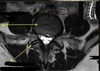

10

Q

What is letter A?

A

CSF

11

What is letter B?

SPINAL CORD

12

What is letter C?

LAMINA

13

What is letter D?

DORSAL NERVE ROOT

14

What is letter E?

VENTRAL NERVE ROOT

15

What is letter F?

VERTEBRAL BODY

16

What is letter G?

SPINOUS PROCESS

17

What is letter H?

TRANSVERSE PROCESS

18

What is letter J?

VERTEBRAL ARTERY